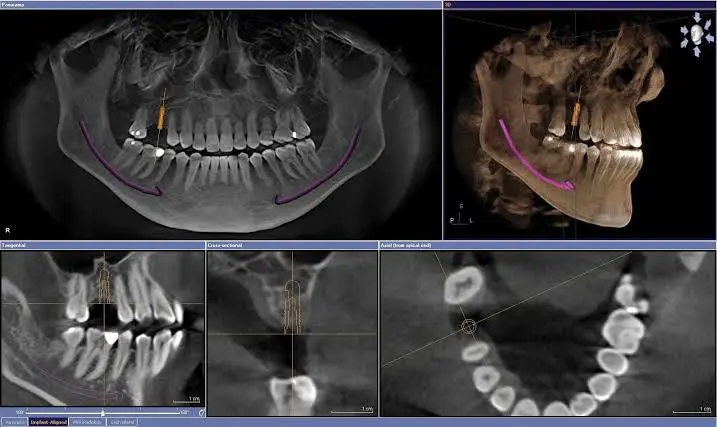

DVT Dental Tomografi Çekimi

Dental Implant Tedavisi